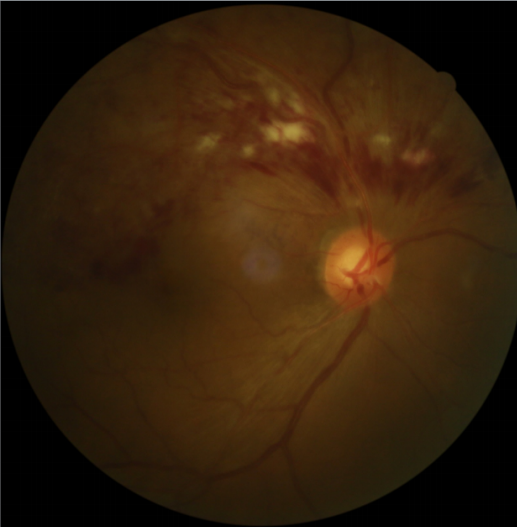

患者劉某,58歲,因右眼視力下降伴變形1月入院。既往有高血壓病,血糖偏高病史,左眼視物不見10餘年(nián),經過眼科主治(zhì)醫(yī)師方(fāng)霏的詳細檢查及眼底造影檢查(chá),發現是患(huàn)上(shàng)了右眼(yǎn)視網膜分支(zhī)靜脈阻塞,右眼黃斑水腫,左眼萎縮(suō)性黃斑(bān)病變。劉大叔入院時右眼視力僅0.1 ,需要使用一種新型的生物製劑(抗 VEGF)治療,方霏主治醫師向患者及家屬交待病情、手術必(bì)要性及相關風險 ,在排除了手術禁忌症後,患者及家屬表示同意手術治療。次日(rì),方霏主(zhǔ)治醫師在(zài)患者表麵麻醉下(xià)進行右眼玻璃體藥物(wù)注射術,術後患者無明顯(xiǎn)特殊不適。4周後複查,右眼黃斑水腫明顯減輕,視力由0.1提高至0.6。玻璃體腔注藥術明顯改善了(le)患者視力,患者劉(liú)大叔表(biǎo)示十(shí)分滿意(yì)。

術前眼底照(zhào)相及眼底造(zào)影FFA